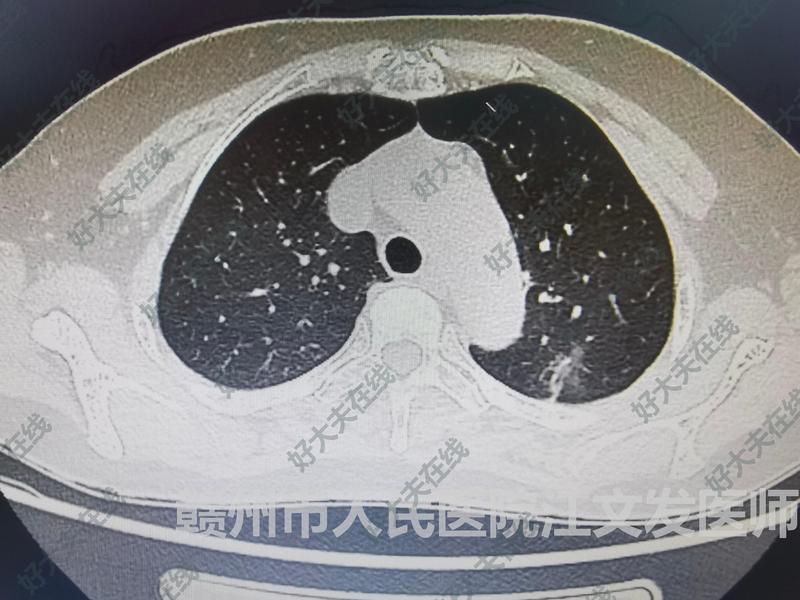

治療前患者67歲女性,2020年胸部CT報告提示陳舊性病灶,23年復查病灶略微增大,但是胸部CT報告仍然提示陳舊性病灶。24年10月份復查胸部CT,發(fā)現(xiàn)病灶明顯增大,來住院手術治療。治療中于2024年10月27日行單操作孔胸腔鏡左肺上葉切除+縱隔淋巴結清掃術。治療后治療后7天患者恢復良好出院。術后病理證實為浸潤性腺癌,含乳頭型和微乳頭型成分,有支氣管侵犯及氣腔播散,肺門淋巴結見癌轉移。分期:pT1cN1M0,IIB期。特別提醒:發(fā)現(xiàn)肺結節(jié),一定要找胸外科的醫(yī)師仔細閱片,決定是不是要盡早手術治療。